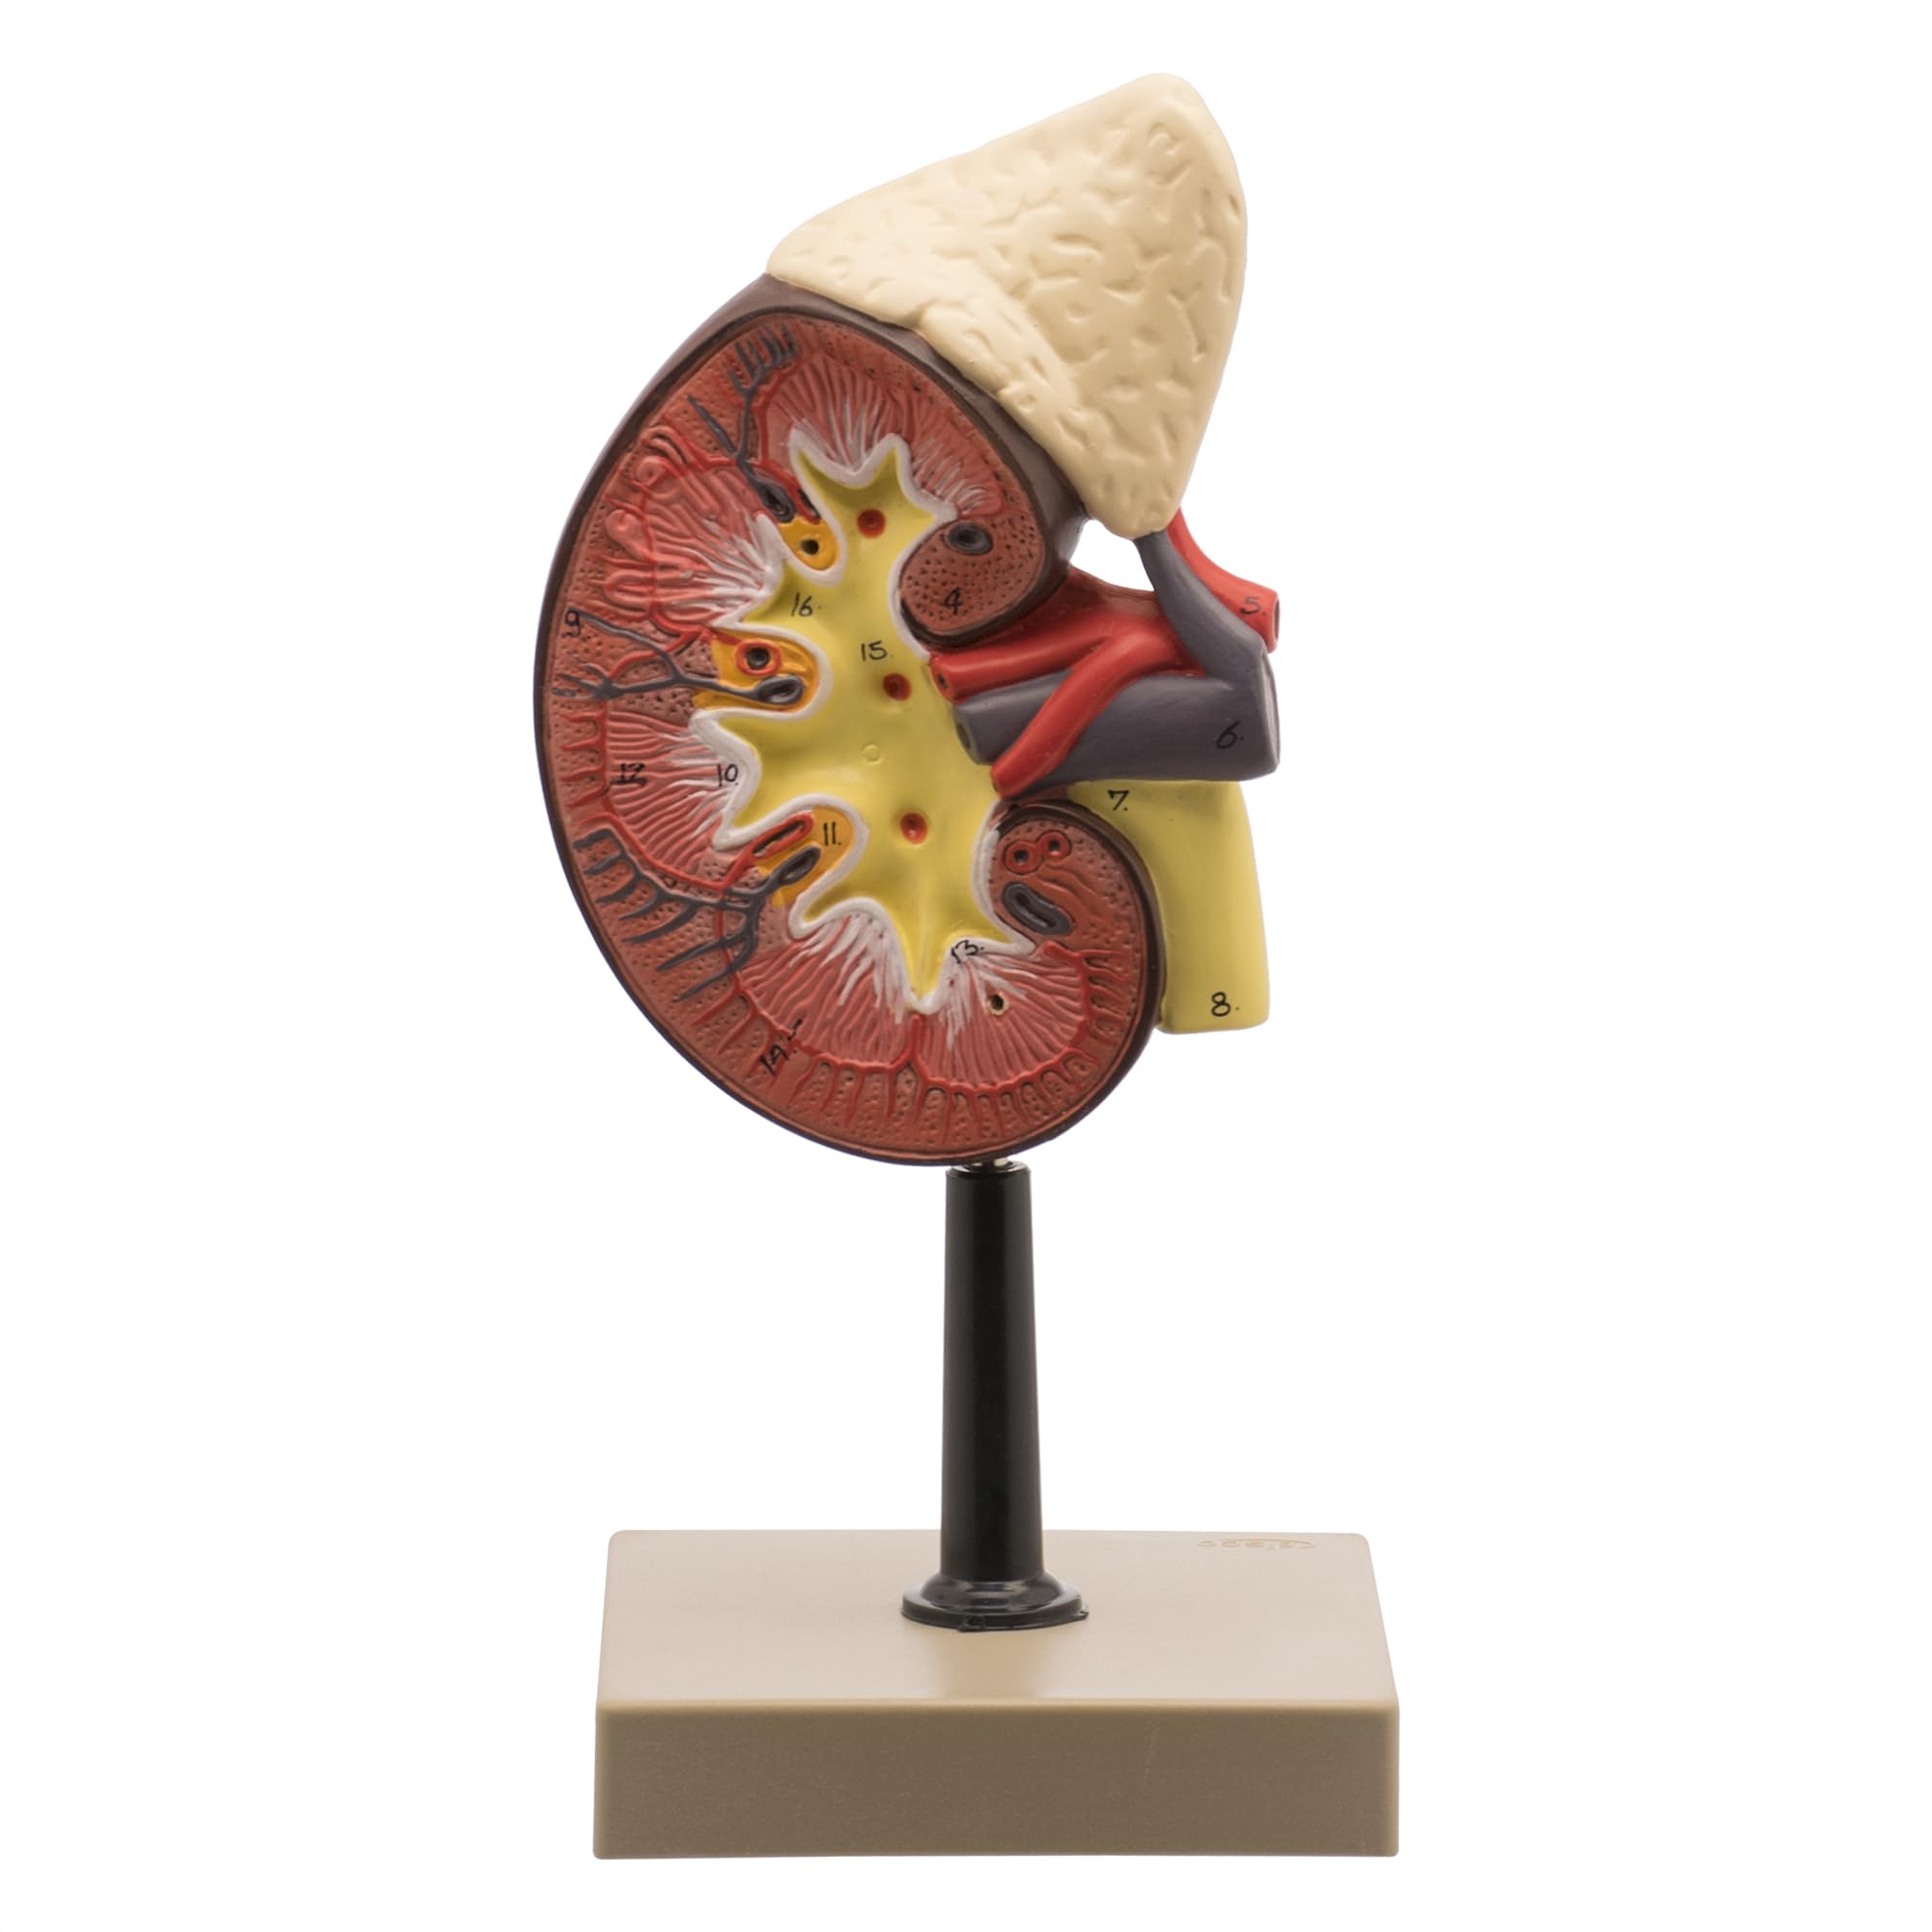

This is a life size replica model of a human kidney that hightlights the interworking of how the human kidney functions. Structures that are emphasized are the adrenal glands, the renal and adrenal vessels which help show how blood is filtered inside of the Bowman’s capsels. The removable front half of the model helps showcase the renal cortex, medulla, and the division of the renal artery down to the capillary level. The model is mounted on a solid base for decades of student use.

- LIFE-SIZE REPRESENTATION – Offers an accurate and tangible study tool for the human kidney and adrenal gland, perfect for students and healthcare professionals.

- DETAILED INTERNAL STRUCTURE – Removable front half allows a deeper look into the kidney’s cortex, medulla, vessels, and renal pelvis for an immersive learning experience.

- EDUCATIONAL ACCOMPANIMENT – Comes with a detailed key for easy identification of 16 distinct structures, boosting understanding and retention.

- ENHANCED VISIBILITY – Generous sizing ensures that even the smallest details are visible, making it easier to explain and study complex internal anatomy.

- STURDY & DETAILED MODEL – Constructed to withstand regular use in educational environments, this model delivers durability along with anatomically correct features.